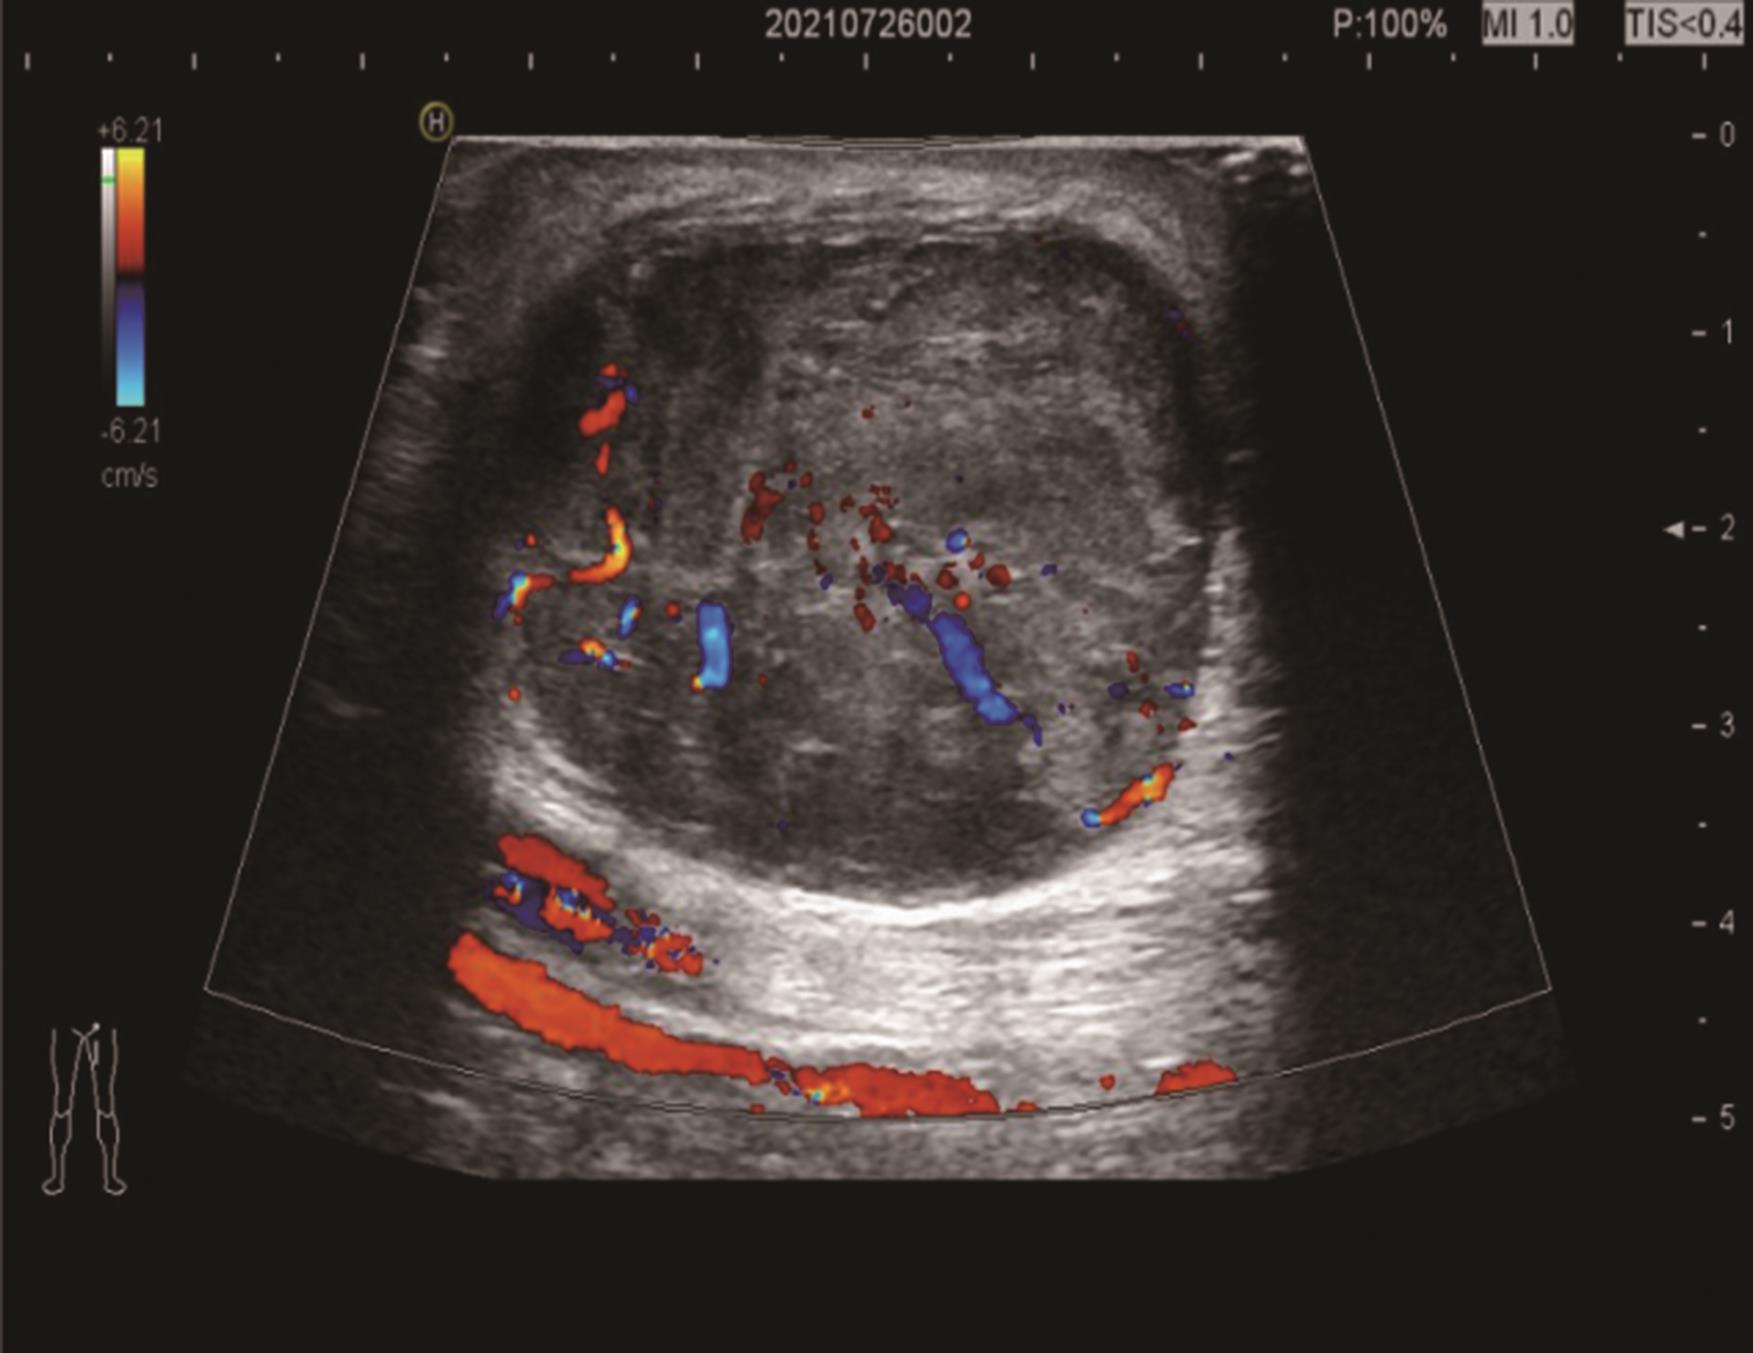

• 探讨增强CT在鉴别胆囊癌侵犯肝脏与肝癌累及胆囊病变中的应用价值

摘要:目的 探讨增强电子计算机断层扫描(computer tomography,CT)在胆囊癌侵犯肝脏与肝癌累及胆囊病变中的鉴别诊断价值。方法 收集2012年2月到2022年2月重庆医科大学附属第一医院115例患者临床及影像学资料,其中胆囊癌侵犯肝脏病例69例,肝癌累及胆囊病例46例,记录性别、年龄、肿瘤大小、肿瘤边界、胆囊形态、肝硬化、胆管扩张、肿瘤内或胆管系统内高密度影、门静脉癌栓、强化方式、强化程度、淋巴结肿大及远处转移共13个观察指标,并进行统计学分析。结果 性别(P=0.007)、年龄(P=0.002)、肿瘤大小(P=0.003)、肝硬化(P<0.001)、肿瘤内或胆管系统内高密度影(P=0.013)、门静脉癌栓(P<0.001)、强化方式(P<0.001)及淋巴结肿大(P=0.034)有统计学差异。通过回归分析筛选出年龄(敏感度为0.812,特异度为0.457)、肿瘤大小(敏感度为0.630,特异度为0.696)、门静脉癌栓(敏感度为0.326,特异度为0.957)、淋巴结肿大(敏感度为0.681,特异度为0.522)为显著分类指标,联合4个观察指标的参数绘制受试者工作特征(receiver operating characteristic,ROC)曲线,曲线下面积(area under the curve,AUC)为0.770,敏感度为0.674,特异度为0.826。结论 增强CT在鉴别胆囊癌侵犯肝脏与肝癌累及胆囊病变时,性别、年龄、肿瘤大小、肝硬化、肿瘤内或胆管系统内高密度影、门静脉癌栓、强化方式及淋巴结肿大有鉴别价值,同时结合年龄、肿瘤大小、门静脉癌栓及淋巴结肿大有助于提高鉴别诊断能力。